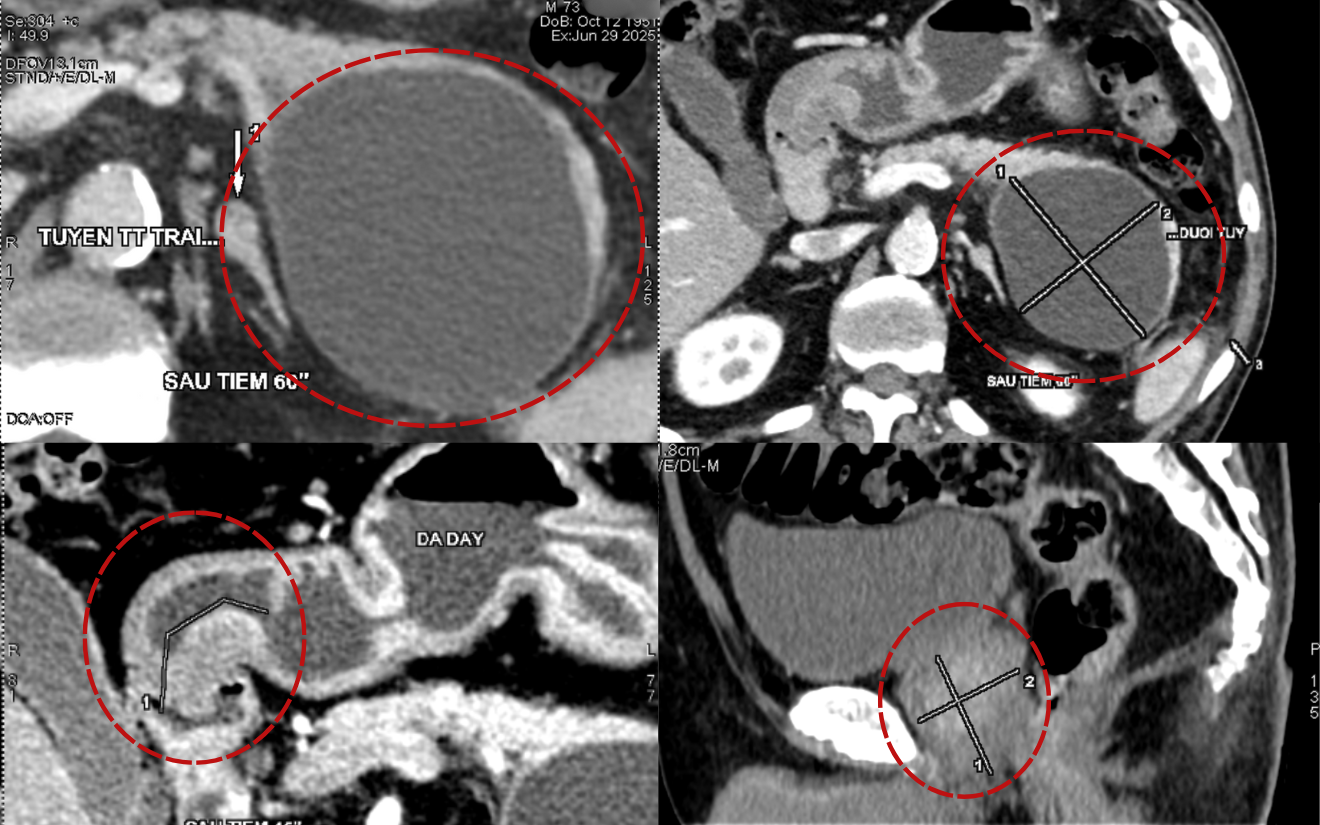

Bệnh nhân Phạm T, 76 tuổi, thăm khám tại BVĐK Hồng Ngọc trong tình trạng đau nóng râm ran vùng thượng vị, chán ăn, mệt mỏi. Kết quả nội soi và chụp CT phát hiện bệnh nhân có tổn thương tiêu hóa đa cơ quan: tổn thương loét vùng hang vị dạ dày, ung thư đại tràng sigma, và có nang tụy đường kính khoảng 10cm. Đây là một bệnh nhân tuổi cao, có nhiều bệnh lý nền phức tạp như đái tháo đường biến chứng suy thận, hẹp mạch vành, tăng huyết áp, rối loạn mỡ máu, viêm gan B… khiến việc điều trị gặp nhiều thách thức. Do vậy bệnh nhân đã được hội chẩn liên chuyên khoa để đề ra các biện pháp điều trị tối ưu nhất.